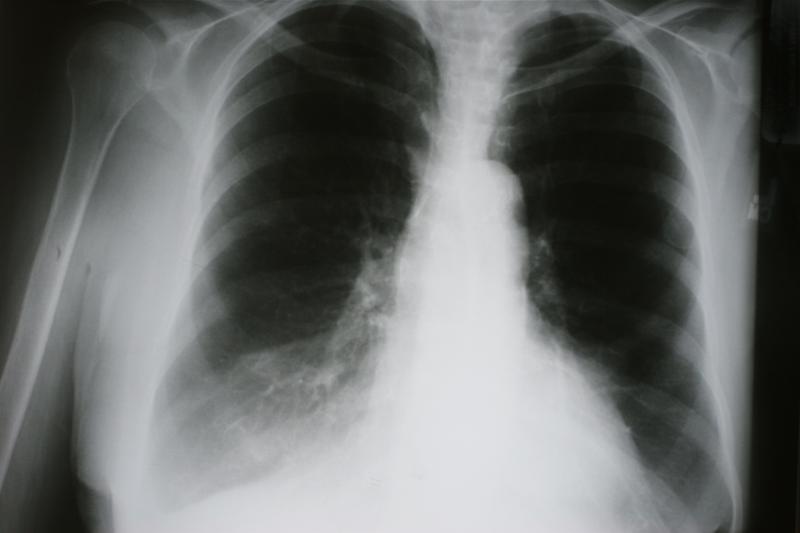

Adding camrelizumab to platinum-based chemotherapy in the neoadjuvant treatment setting appears to improve the rate of pathologic complete response (pCR) in Asian patients with stage IIIA or IIIB non–small cell lung cancer (NSCLC), with manageable toxicity, according to data from the phase II TD-FOREKNOW study.

TD-FOREKNOW included 94 adult patients in China who had resectable stage IIIA or IIIB NSCLC. These patients were randomly assigned to receive three cycles of camrelizumab (200 mg) plus chemotherapy (nab-paclitaxel, 130 mg/m2, and platinum [cisplatin, 75 mg/m2; carboplatin, area under the curve, 5; or nedaplatin, 100 mg/m2]) or chemotherapy alone, followed by surgery after 4 to 6 weeks.